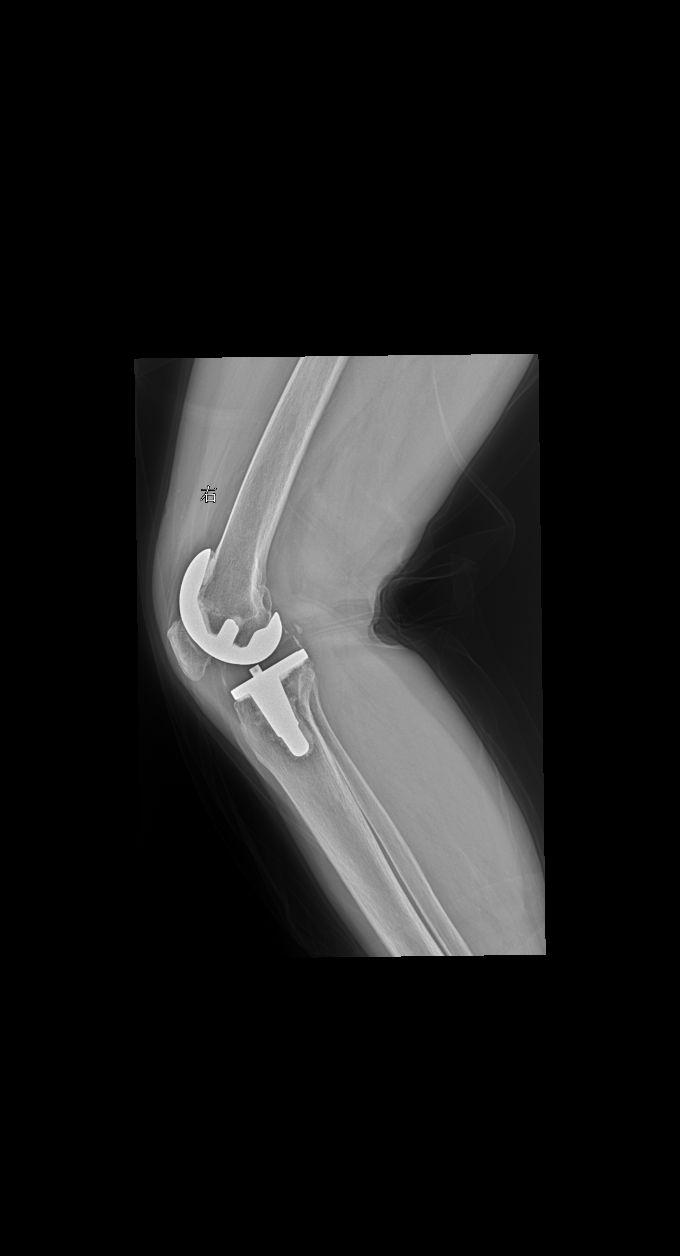

术后 复查 女61

2024-11-08 15:58:22